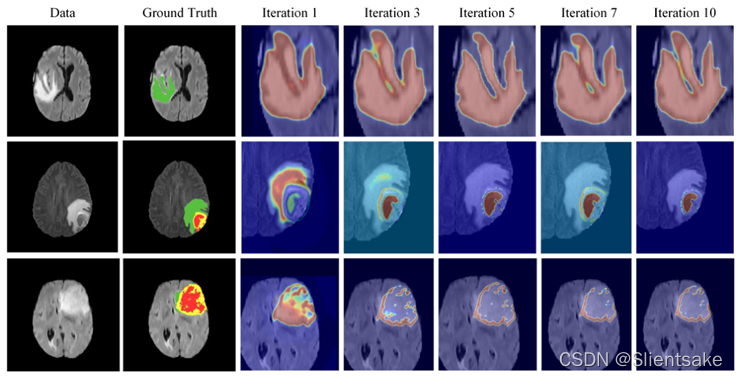

手动设置CG-ACRF平均场近似中的迭代次数。由于平均场近似只能保证局部最优,作者考察了不同迭代次数的结果。表二报告了使用不同迭代次数(即1、3、5、7和10)的定量结果。随着迭代次数的增加,提出的模型表现得更好。然而,可以观察到,当迭代次数超过5时,无法获得额外的性能优势。图6呈现了分割期间的概率图,其中浅色代表具有较低概率的区域,而深色代表具有较高概率的区域。可以观察到,仅使用一次迭代,CANet就可以使用融合的特征图来勾勒出感兴趣的区域。通过将迭代次数增加到3或5,CG-ACRF可以逐渐提取最佳特征图,从而实现精确分割。进一步将迭代次数增加到7和10,但没有进一步改进。因此,将迭代次数设置为5,作为分割性能和使用的参数数量之间的有效折衷。

表2:关于DICE、敏感性、特异性和HAUSDORFF95,通过CG-ACRF平均场近似对BRATS2017训练集进行五次交叉验证,得出不同迭代次数的定量结果。最佳结果以粗体显示,亚军结果以下划线显示。

图6:不同迭代次数生成得到的注意力图